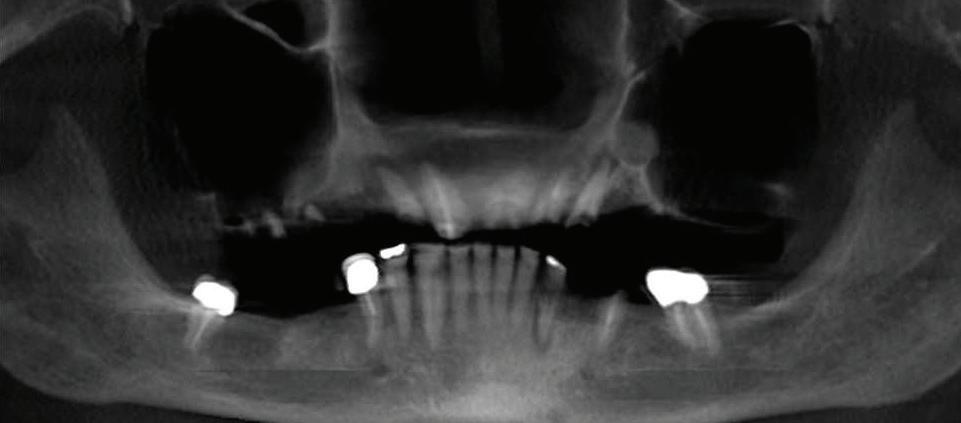

When a patient goes to their TMJ doctor, it is vitally important to make sure that certain technologies are used in order to get a good diagnosis and even greater treatment. In this article we will be looking at the merits of the dedicated Tesla coil, the x-rays to look at the jaw joints, the digital impression scanner, and the ever so important computer.

When it comes to getting a really great MRI of your TM joints, it is really important to be sure that the imaging center has a Tesla coil dedicated for this kind of work because it is so sensitive and can allow us to see the articular discs much better than some older technology. In too many cases, the MRI is done with an inferior machine and the reading is simply not that precise. This will often lead to a misdiagnosis and a path of treatment that costs lots of money, time, and frustration.

Another piece of technology in getting proper TMJ treatment involves the x-ray equipment. It is important first of all to go with “green” technology, i.e. low dose radiation and three-dimensional imaging. The 3-D imaging comes in really handy when the doctor wants to see what’s going on behind and around the corners of various bones, especially the condyle or jaw bone. This information helps when trying to correlate to the findings of the MRI; do the slipped discs make sense and is that why the jaw bone has shifted in that direction?

A very fun and very special advancement when it comes to doing braces to finish up a TMJ patient is the digital impression system. This system basically uses a camera to videotape the teeth and the computer effectively “stitches” all the videos together to show the lab what the teeth look like. In addition, the digital impressions are the most accurate way to see the teeth and jaw bones. Then, the braces manufacturer

Why TMJ Technology Is So Important

uses a device to “cut’ each bracket to the best fit possible for every individual tooth. This means that each bracket is custom made, by hand (the hand of a computer guided laser that is) to the proper tip and torque needed to achieve the best result in the shortest time possible. Think of it like GPS for your trip up to Canada

the computer will design the least difficult, quickest, and most efficient path to get you there.

Let’s not forget to give mention to our old friend, the computer, which has advanced so much in recent years that we have become used to it running on terabytes, not kilobytes, of storage and how fast

the processors have become. Without the computer, we could not show the patient the wonderful world of digital x-rays and show them how their progress has changed. The computer and all these other technologies have surely changed our world, and made treatment better and easier for patients.